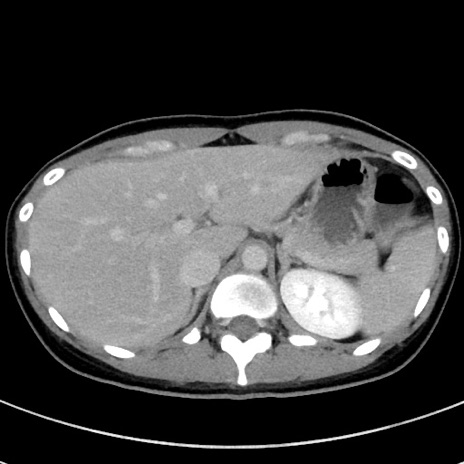

症例17(横断像)

【症例】20歳代女性

【主訴】嘔吐、下腹部痛

【現病歴】昨日夕食後に嘔吐し下腹部痛が出現。本日になっても嘔吐持続し改善しないため来院。

【身体所見】意識清明、BT 37.2℃、BP 108/67mmHg、腹部:平坦、やや硬、下腹部正中から右にかけて圧痛あり、反跳痛軽度あり、tapping pain(+)。

【データ】WBC 13600、CRP 14.94